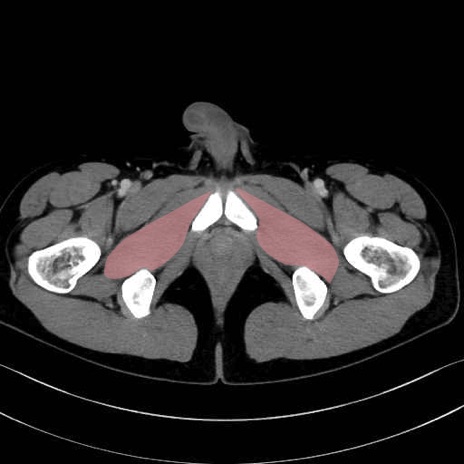

外閉鎖筋 (Obturator externus)